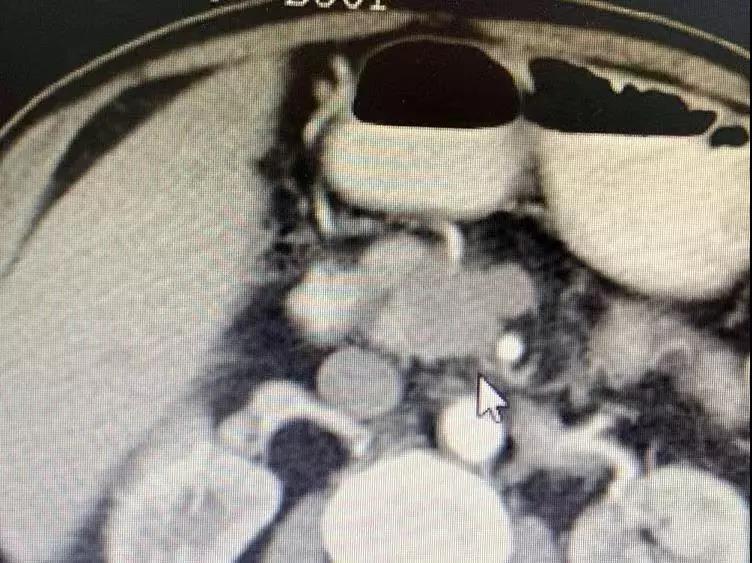

До операции опухоль поджелудочной железы окружает кровеносные сосуды и обнаруживаются метастазы в брюшных лимфатических узлах.

Медсестра сказала мне, что он и его семья были очень добрыми, и они улыбались и кивали вам, когда приветствовали. Было сказано, что он внезапно почувствовал боль в верхней части живота в апреле этого года. Позже в мае он прошел обследование в местной больнице. Неподтвержденная масса в поджелудочной железе размером 3 см была обнаружена вблизи верхней брыжеечной вены, которая предположительно была раком поджелудочной железы. 25 июля у него было еще одно обследование, и его состояние ухудшилось. Опухоль проникла в верхнюю брыжеечную вену и артерию; многочисленные маленькие лимфатические узлы были обнаружены перед полой веной и вблизи аорты. Из-за ограниченных медицинских ресурсов лучшего лечения в Непале не было. Затем его врач порекомендовал ему Онкологическую больницу Фуда.

Необратимая электропорация при опухоли поджелудочной железы